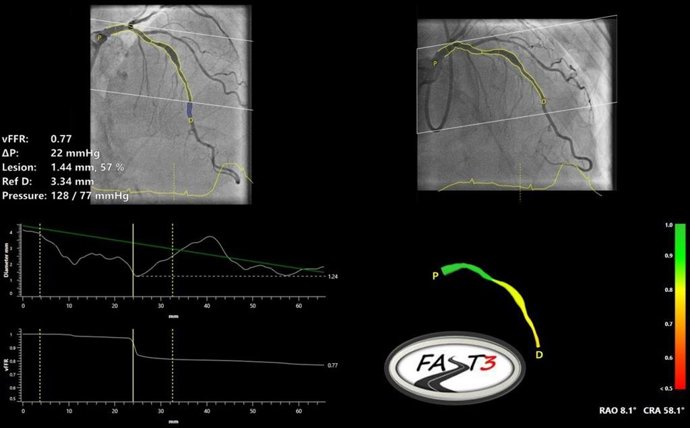

CAAS vFFR Software

CAAS vFFR (Pie Medical Imaging, Maastricht, Países Bajos) es un programa informático de FFR basado en angiografía que permite la evaluación fisiológica de la estenosis coronaria intermedia sin necesidad de utilizar un cable de presión ni adenosina. El valor vFFR puede calcularse únicamente con dos proyecciones angiográficas y la presión de la raíz aórtica. Esta vFFR tiene una alta correlación y precisión diagnóstica en comparación con las mediciones invasivas de FFR y NHPR basadas en cables, y los resultados de la vFFR han demostrado ser altamente reproducibles.